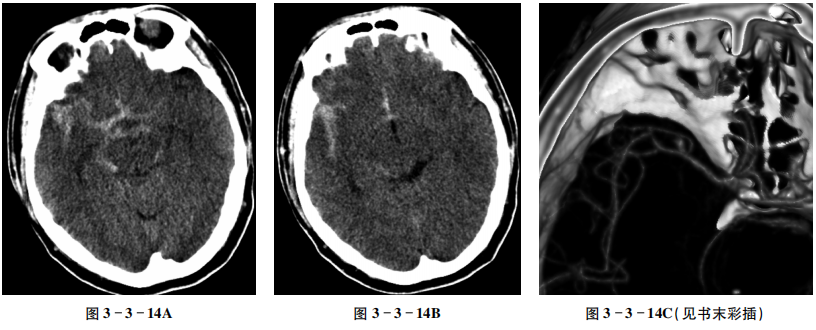

【CT征象】

平扫右侧外侧裂池、环池及四叠体池右侧见条状高密度影。三脑室前部亦见条状高密度影(图3-3-14A、B)。头颅CTA成像示右侧大脑中动脉M2段分叉处管腔呈囊袋状膨隆(图3-3-14C)。

【重要征象】

脑沟、脑裂及脑池铸型高密度影,邻近脑动脉管腔局限性突起。

【CT拟诊】

右侧大脑中动脉M2段分叉处动脉瘤破裂,蛛网膜下腔出血。

【最终诊断】